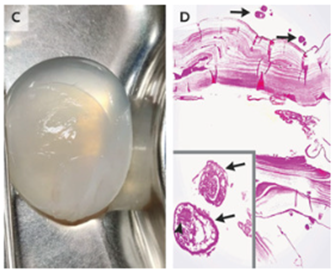

破裂を避けるために生理食塩水洗浄を使用し嚢胞壁を脳から分離した(C)。

病理検査では娘嚢胞(D)および鉤状突起(矢印)を有する原虫を認めた。